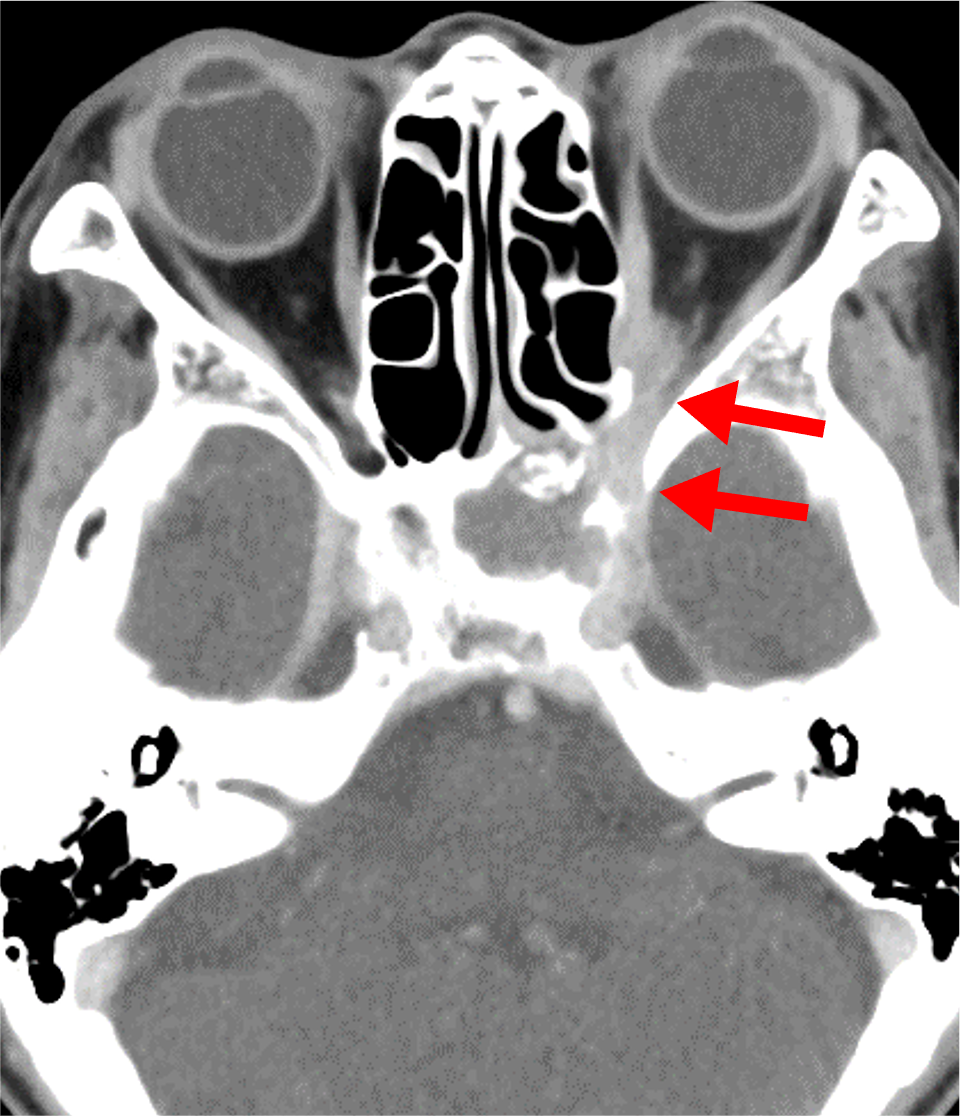

1か月前からの左眼痛、2週間前からの視野異常があり、前医で蝶形骨洞真菌症と診断された。視力障害の急速な進行と左内側視野欠損を来たしたため、当院に紹介された。造影CTにて左蝶形骨洞から左海綿静脈洞・眼窩尖部に浸潤する浸潤性真菌症を指摘された。緊急手術が施行され、病変から糸状様真菌が検出された。

急性浸潤性真菌性副鼻腔炎は臨床経過が4週間以内と急速に進行する病態を示す。骨破壊を伴って副鼻腔から眼窩・海綿静脈洞・頭蓋内に浸潤が見られる。また血管侵襲性が強く、時に仮性動脈瘤形成や動脈狭窄・閉塞、血栓形成を引き起こす。血管に沿って進展し、骨破壊を伴わずに副鼻腔外に炎症が浸潤する場合がある。

造影CTでは骨破壊の有無、副鼻腔外への炎症浸潤、また仮性動脈瘤や動脈狭窄・閉塞、血栓形成を評価する。海綿静脈洞は動脈性病変、静脈洞血栓、炎症浸潤が混在する可能性があり、早期動脈相・後期動脈相・平衡相を撮像することでこれらを鑑別する。